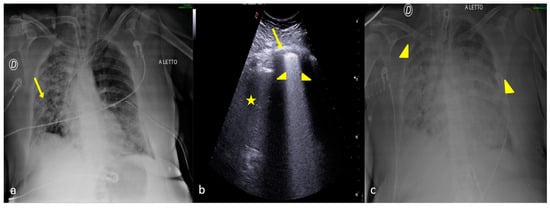

4. Checking and Monitoring the Devices